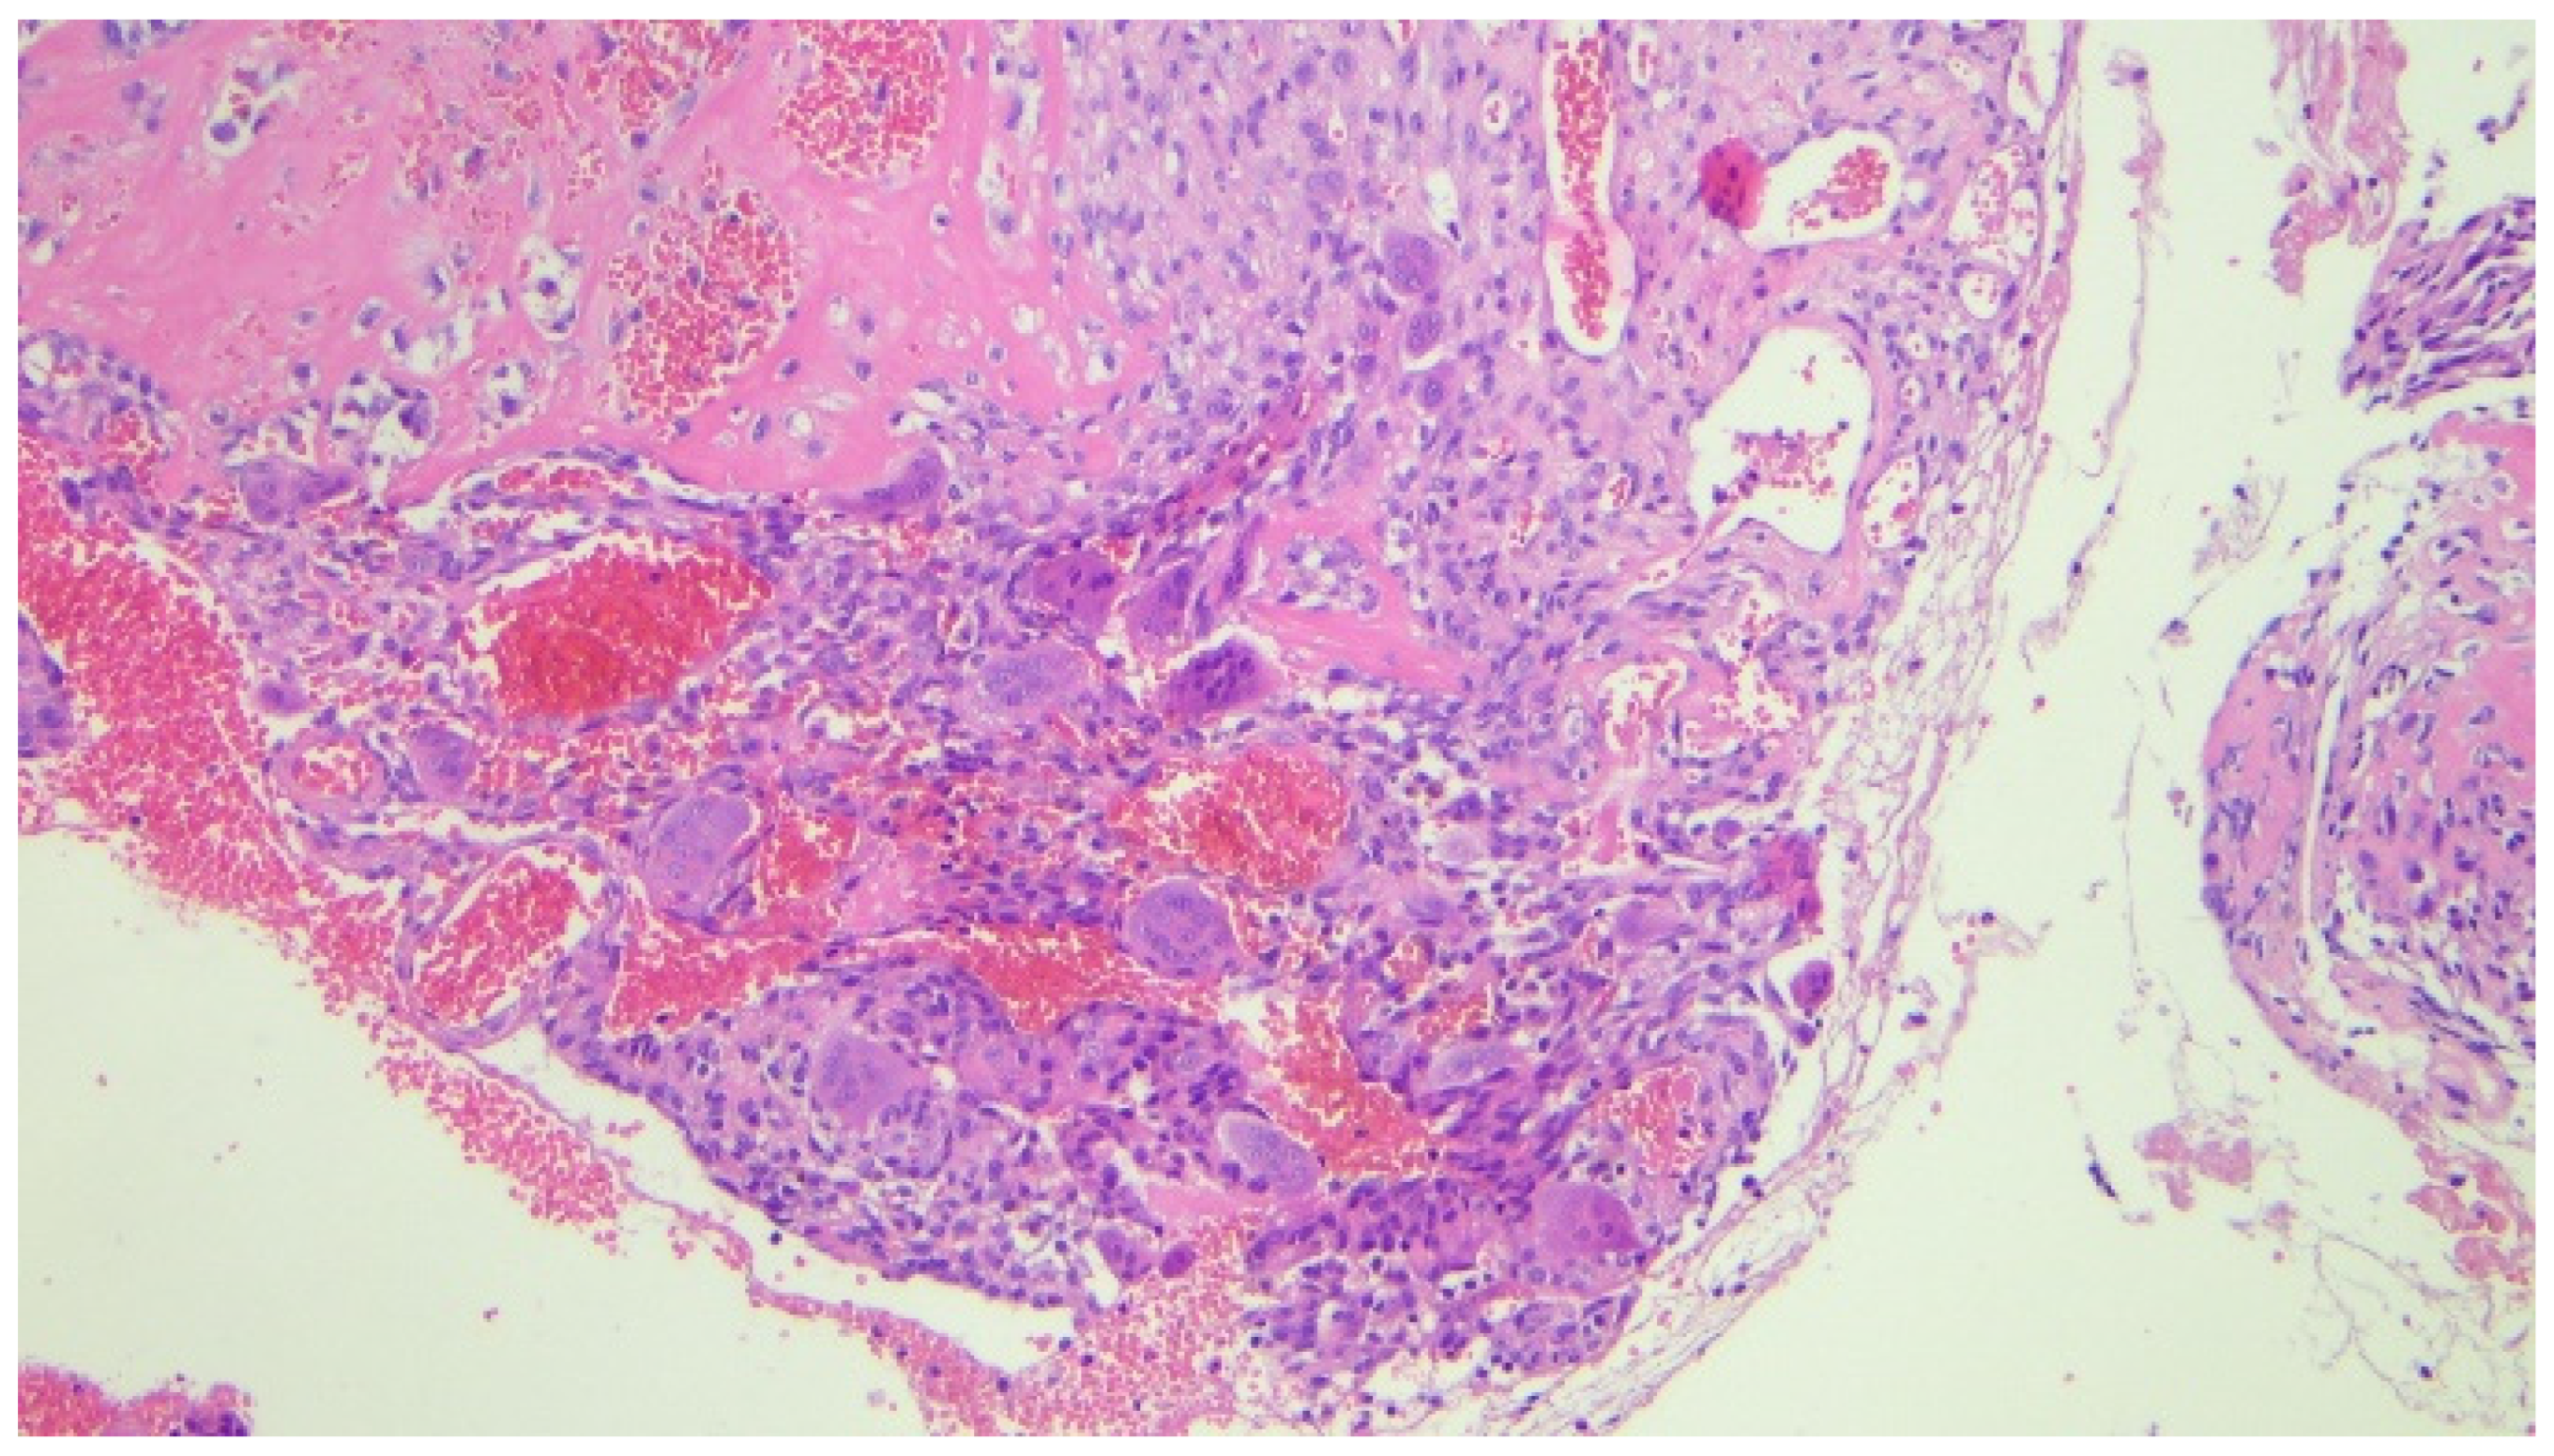

3. Case Report